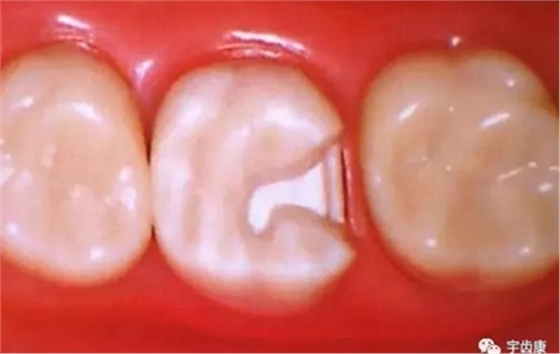

箱型固位形

輔助固位形的制約作用

增加牙體抗力形的措施